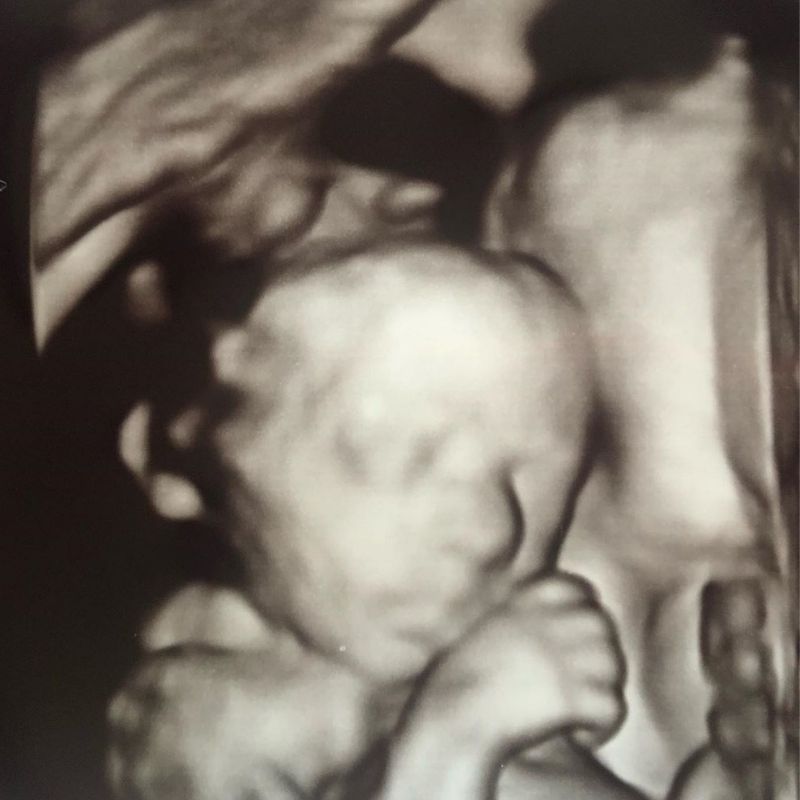

People don’t talk so much about Luna these days, about what she looked like, smelt like, how much she weighed, about our experience. And that’s ok, I can’t expect people to still be as curious or feel the need to mention her as much as I want or need them to. So this blog is my offload. There for when I need it, when I need to release some of the heaviness and dislodge that lump in my throat from time to time. It’s there for when I need to have my mind flooded with thoughts of her and only her. It’s my therapy, and my way of showing her, and the world, that I still love her as much today as first day I heard her heart beating.